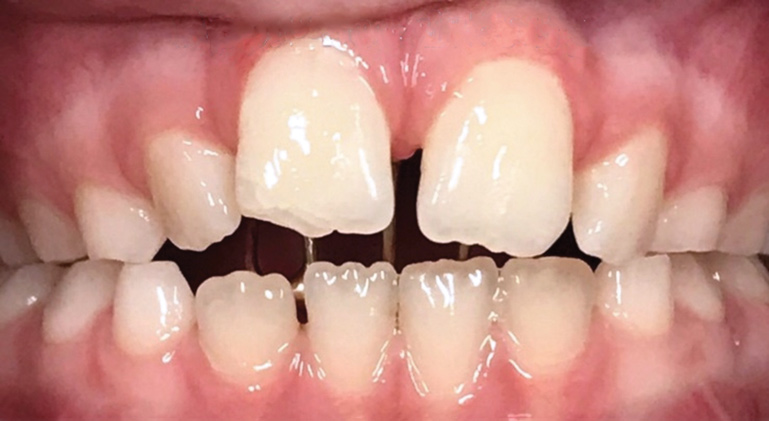

Fig 9. Anteroposterior view of class II (Fig 9) and class III (Fig 10) malocclusion. Arrows indicate positions of the mesial maxillary cusp and embrasure between the mandibular molar cusps. In class II malocclusion the maxillary molar is more anteriorly positioned, while in class III the mandibular molar is more anteriorly positioned.

Figure 9

Fig 10. Anteroposterior view of class II (Fig 9) and class III (Fig 10) malocclusion. Arrows indicate positions of the mesial maxillary cusp and embrasure between the mandibular molar cusps. In class II malocclusion the maxillary molar is more anteriorly positioned, while in class III the mandibular molar is more anteriorly positioned.

Figure 10

Class II malocclusions (Figure 9) may be treated to reduce risk of dental trauma of protruding maxillary incisors or to break a lip trap habit. Some devices used for this purpose include headgears or functional appliances. Many orthodontists may wait to treat class II malocclusions in the permanent dentition because studies find inconclusive evidence of the effectiveness of phase I treatment.28 Early intervention is a strong consideration for class III malocclusion (Figure 10), with the goal of avoiding surgical treatment for either an adolescent or adult. This approach takes into consideration psychological-social concerns as well with regard to balancing facial disproportions and correcting the appearance of an "underbite" and/or prominent lower jaw.29 However, because there is a genetic component, surgery cannot be ruled out as a comprehensive treatment option. An early intervention would include facemask therapy with RPE to orthopedically protract and widen the upper jaw.